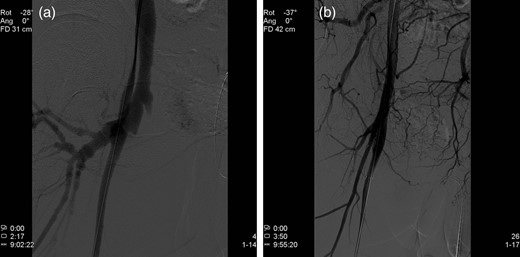

Two weeks postoperatively, reinvestigation of previous CT scans showed rapid contrast filling in the inferior caval vein (Fig. 1a) as well as the right common iliac vein (Fig. 1b), almost simultaneously with the abdominal aorta. Recent CT scans showed dissolution of most of the right-sided, ileofemoral deep vein thrombus. Right groin palpation revealed fremissement. Doppler ultrasound demonstrated an unusually large arteriovenous (AV) fistula localized between the cranial part of the superficial femoral artery and the femoral vein. Flow in the fistula was estimated as 11.2 l/min.

(a) CT scan demonstrating rapid contrast filling of the vena cava. (b) CT scan demonstrating contrast filling of the right common iliac vein.